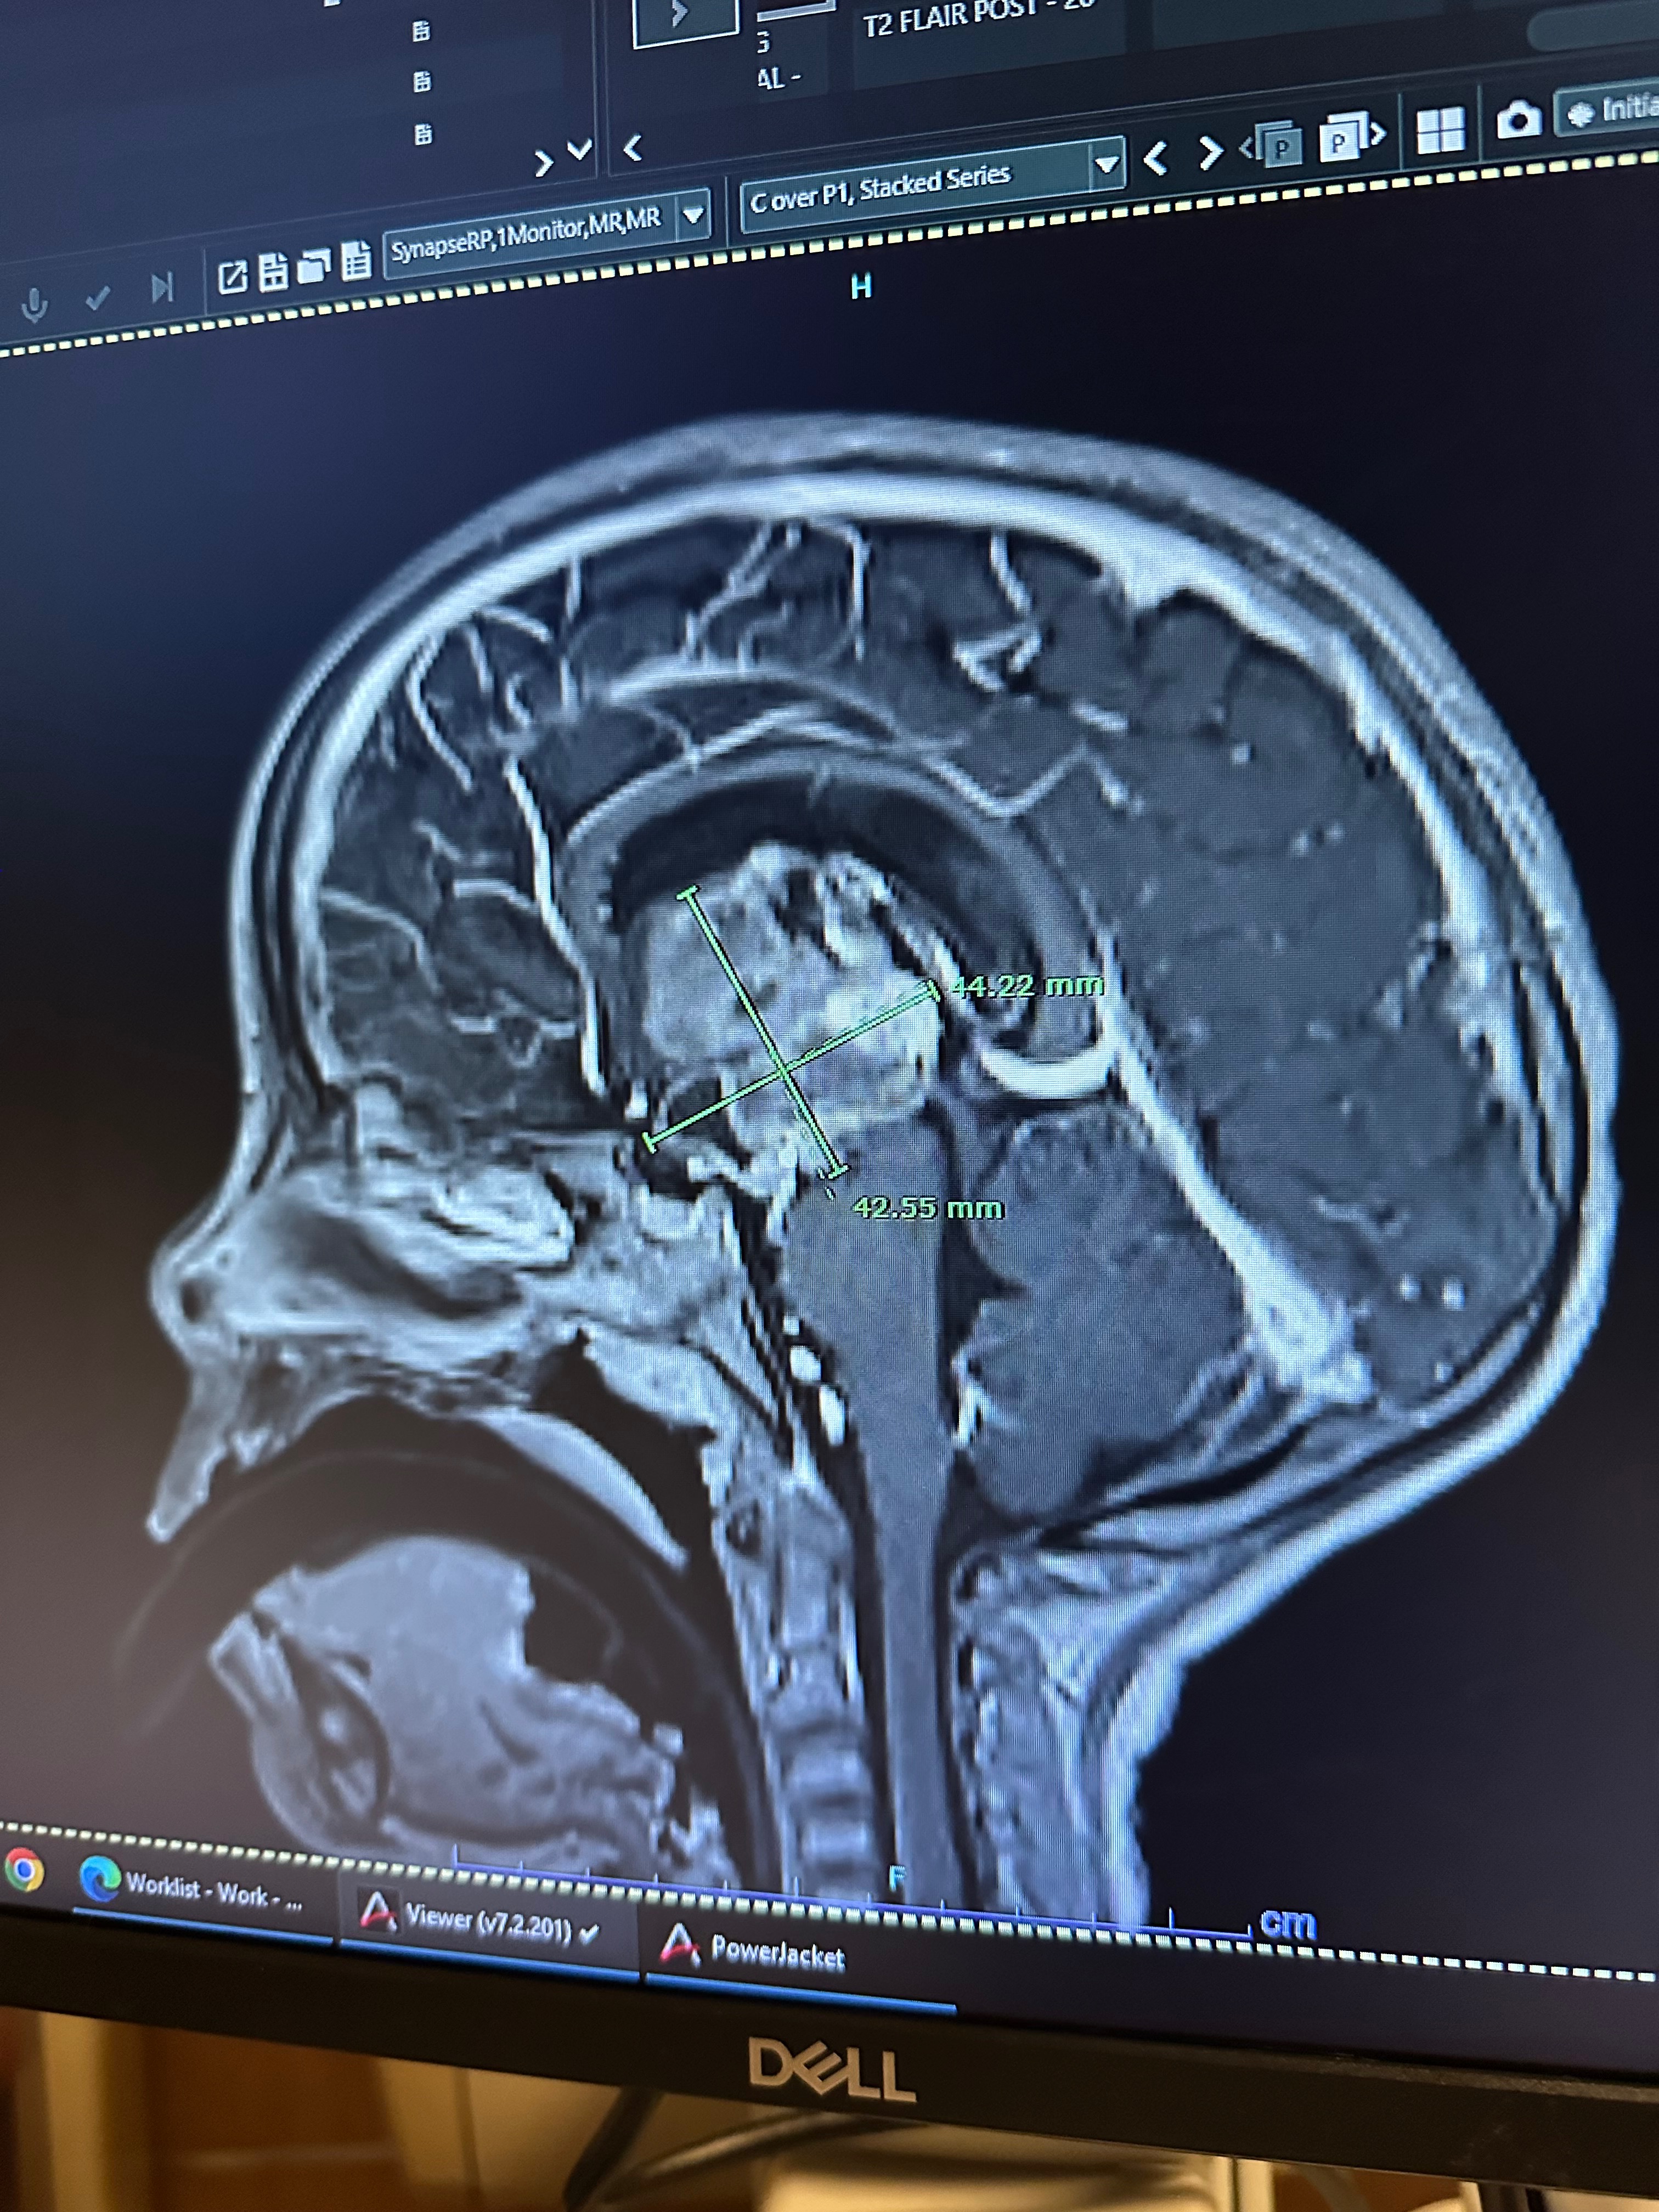

We were told her tumor is a high-grade glioma, an extremely aggressive cancer. We are still waiting for the final pathology report, but based on her imaging, her team is very concerned.

Her second hospitalization began on November 25, and a new MRI showed that the main tumor had grown, multiple new small lesions had appeared in her brain, and tiny spots were also seen on her spine. Part of the tumor presses near the areas of the brain that control vision and body functions, and another part sits on her medulla, likely causing her constant nausea.